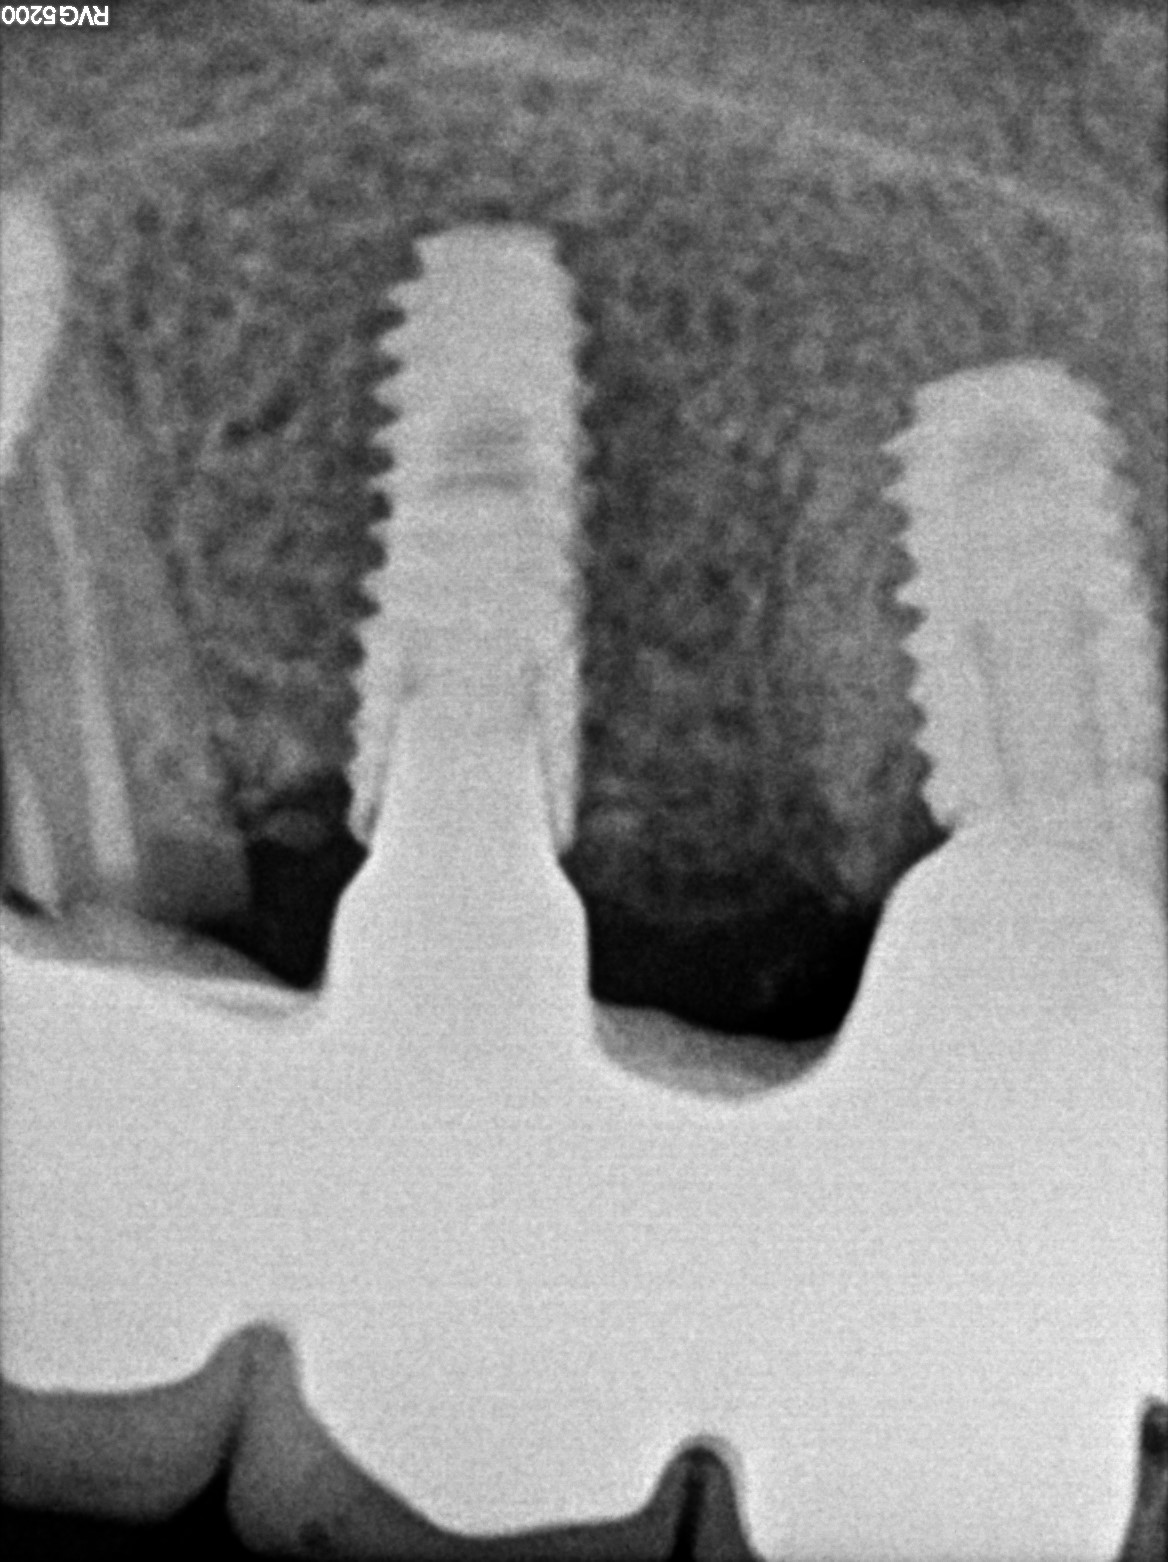

Dental Radiographs FHIR: DocumentReference · LOINC 24641-7

xray_1742374048.jpg

24641-7

| Dental implant placement | 234781005 | D6010 Surgical placement of implant body | — | 2025-03-19 | completed | full mouth implant done @ dr shoebs. came for checkup in 1st and 2nd quad. adv to return if any symptoms | |

| Dental implant placement | 234781005 | D6010 Surgical placement of implant body | — | 2025-03-19 | completed | implant hole filled |